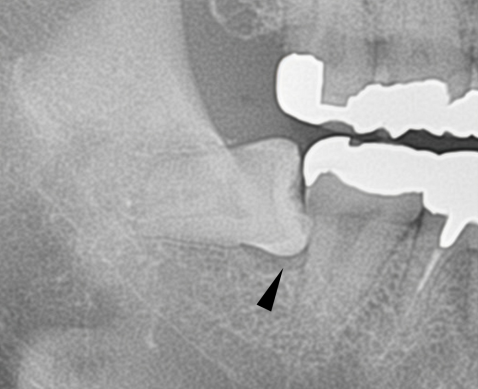

8.手前の歯の根を押す場合、押された歯の根は溶けてしまいます

一番左の親知らずが、大事な隣の歯の根を溶かしてしまいました。

下の親知らずが、前の歯の根を溶かしてしまいました。